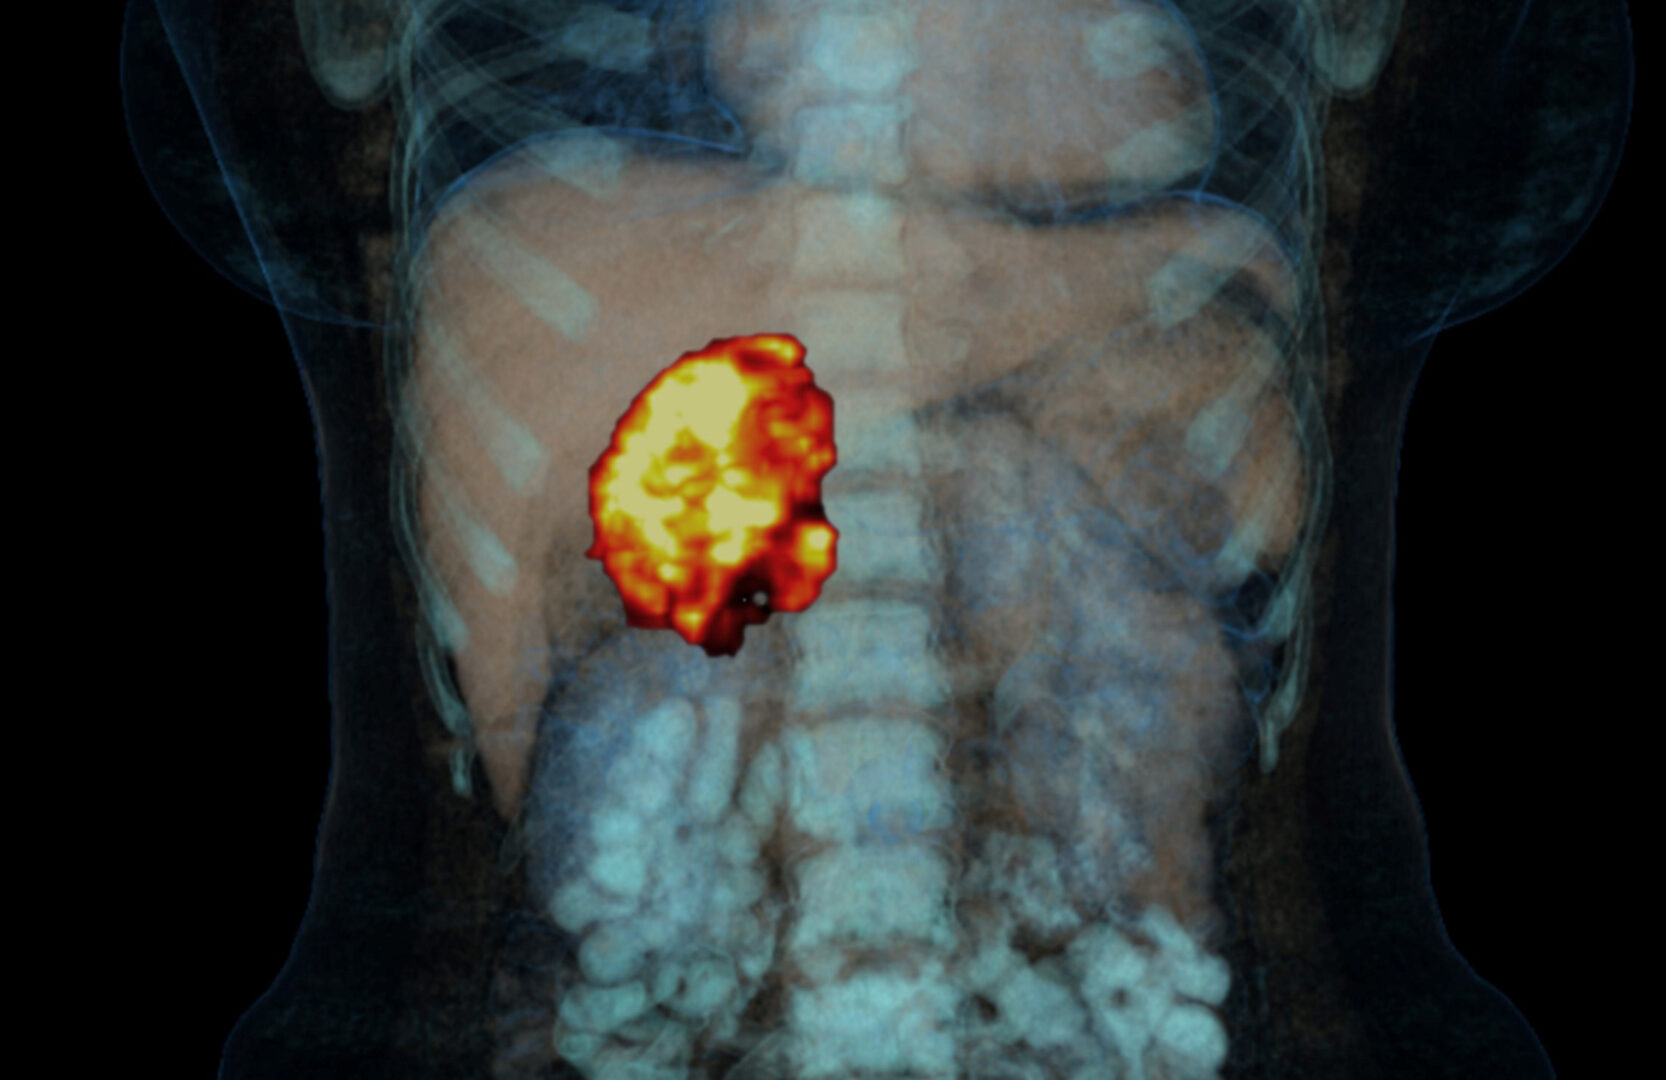

Nebennierenkarzinom: Kein Mitotane bei niedrigem Rückfallrisiko